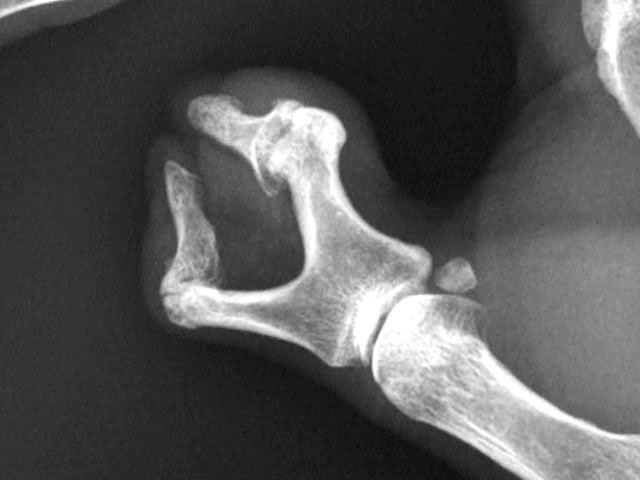

Fractura impactada de húmero .